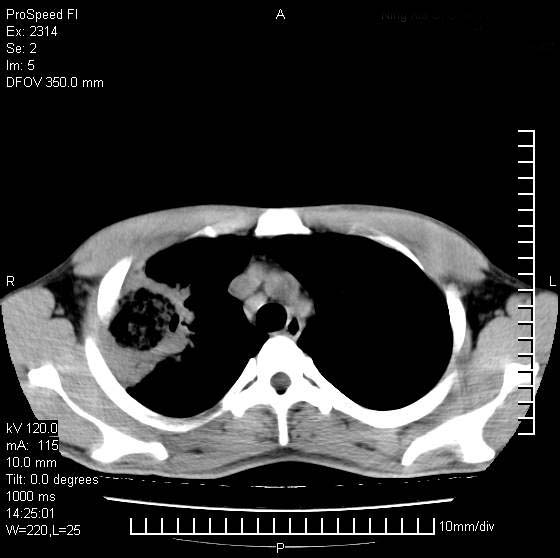

男性,再生障碍性贫血,入院前发热10天,最高40c,右侧胸痛,外院ct示右上,中肺边缘模糊的球性影(就是我现在图中标示的范围),考虑炎症,在我院使用头孢呋辛,洛美沙星10天,高烧消退,自感下午稍有发热,但今天ct示右上,中肺病灶明显扩大,还是考虑炎症,看其中的球型影是否霉菌感染??,是否能排除结核?

右肺中叶外侧段病变,上缘界限不清,下缘锐利,以段性发病为主,内见巨大空洞及空洞内容物,结合病史首先考虑:化脓性肺炎。不除外霉菌感染!

片状高密度影内见空洞影,内可见球形软组织密度影,并有新月征,考虑霉菌感染.

支持右肺上叶、中叶外侧段节段性肺炎伴脓肿形成。